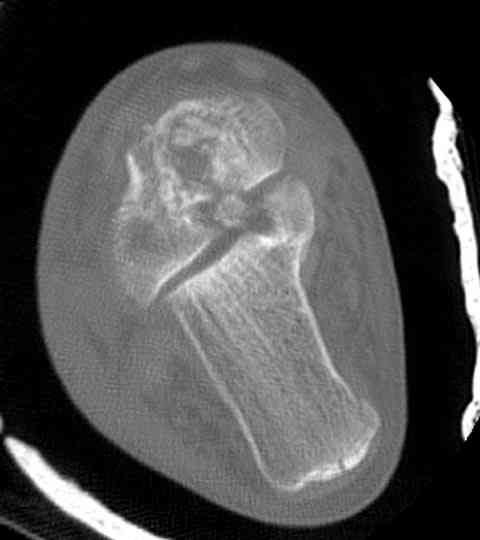

Случай с множественным оскольчатым переломом тарана оперированный из

двойного доступа.

Имя     : talar fx.CT coronal 4.jpg

Тип     : image/jpeg

Размер  : 22512 байтов

Описание: отсутствует

Url     : http://weborto.net:8080/pipermail/ortho/attachments/20070615/61a2112e/attachment-0008.jpg